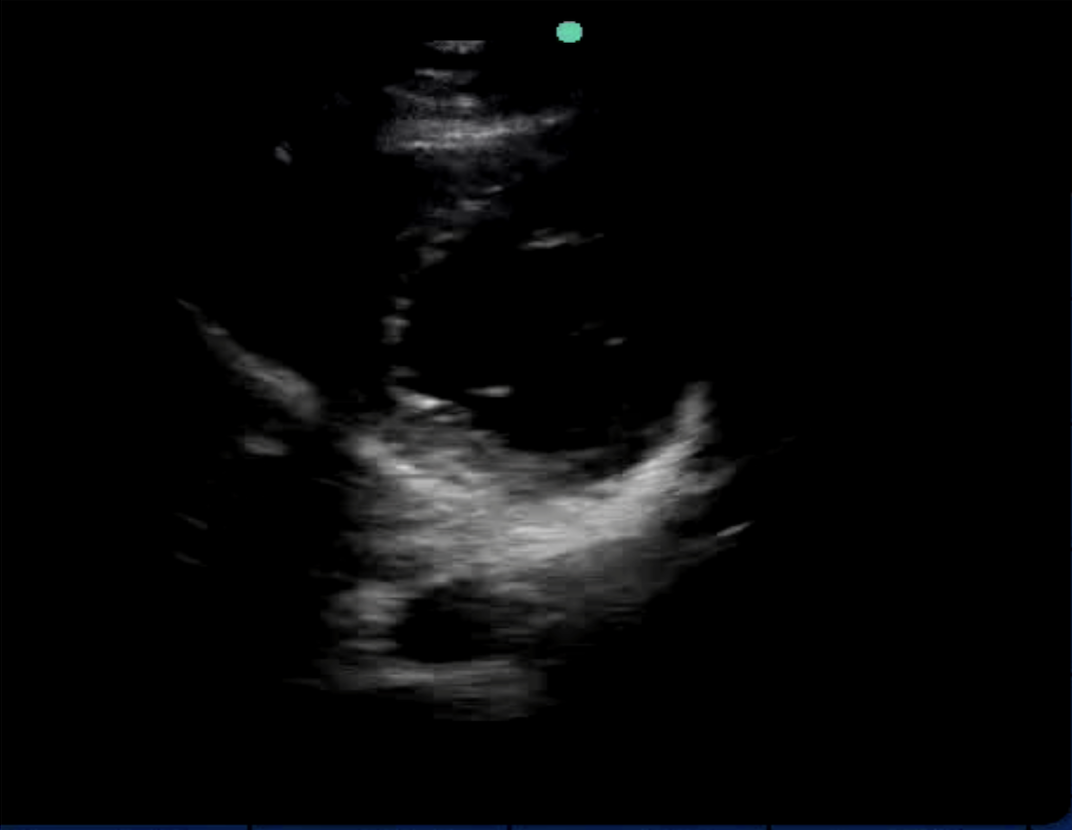

• Venous Doppler (portal and hepatic veins) for congestion assessment

• Venous Doppler (portal/hepatic) to assess back-pressure and venous congestion